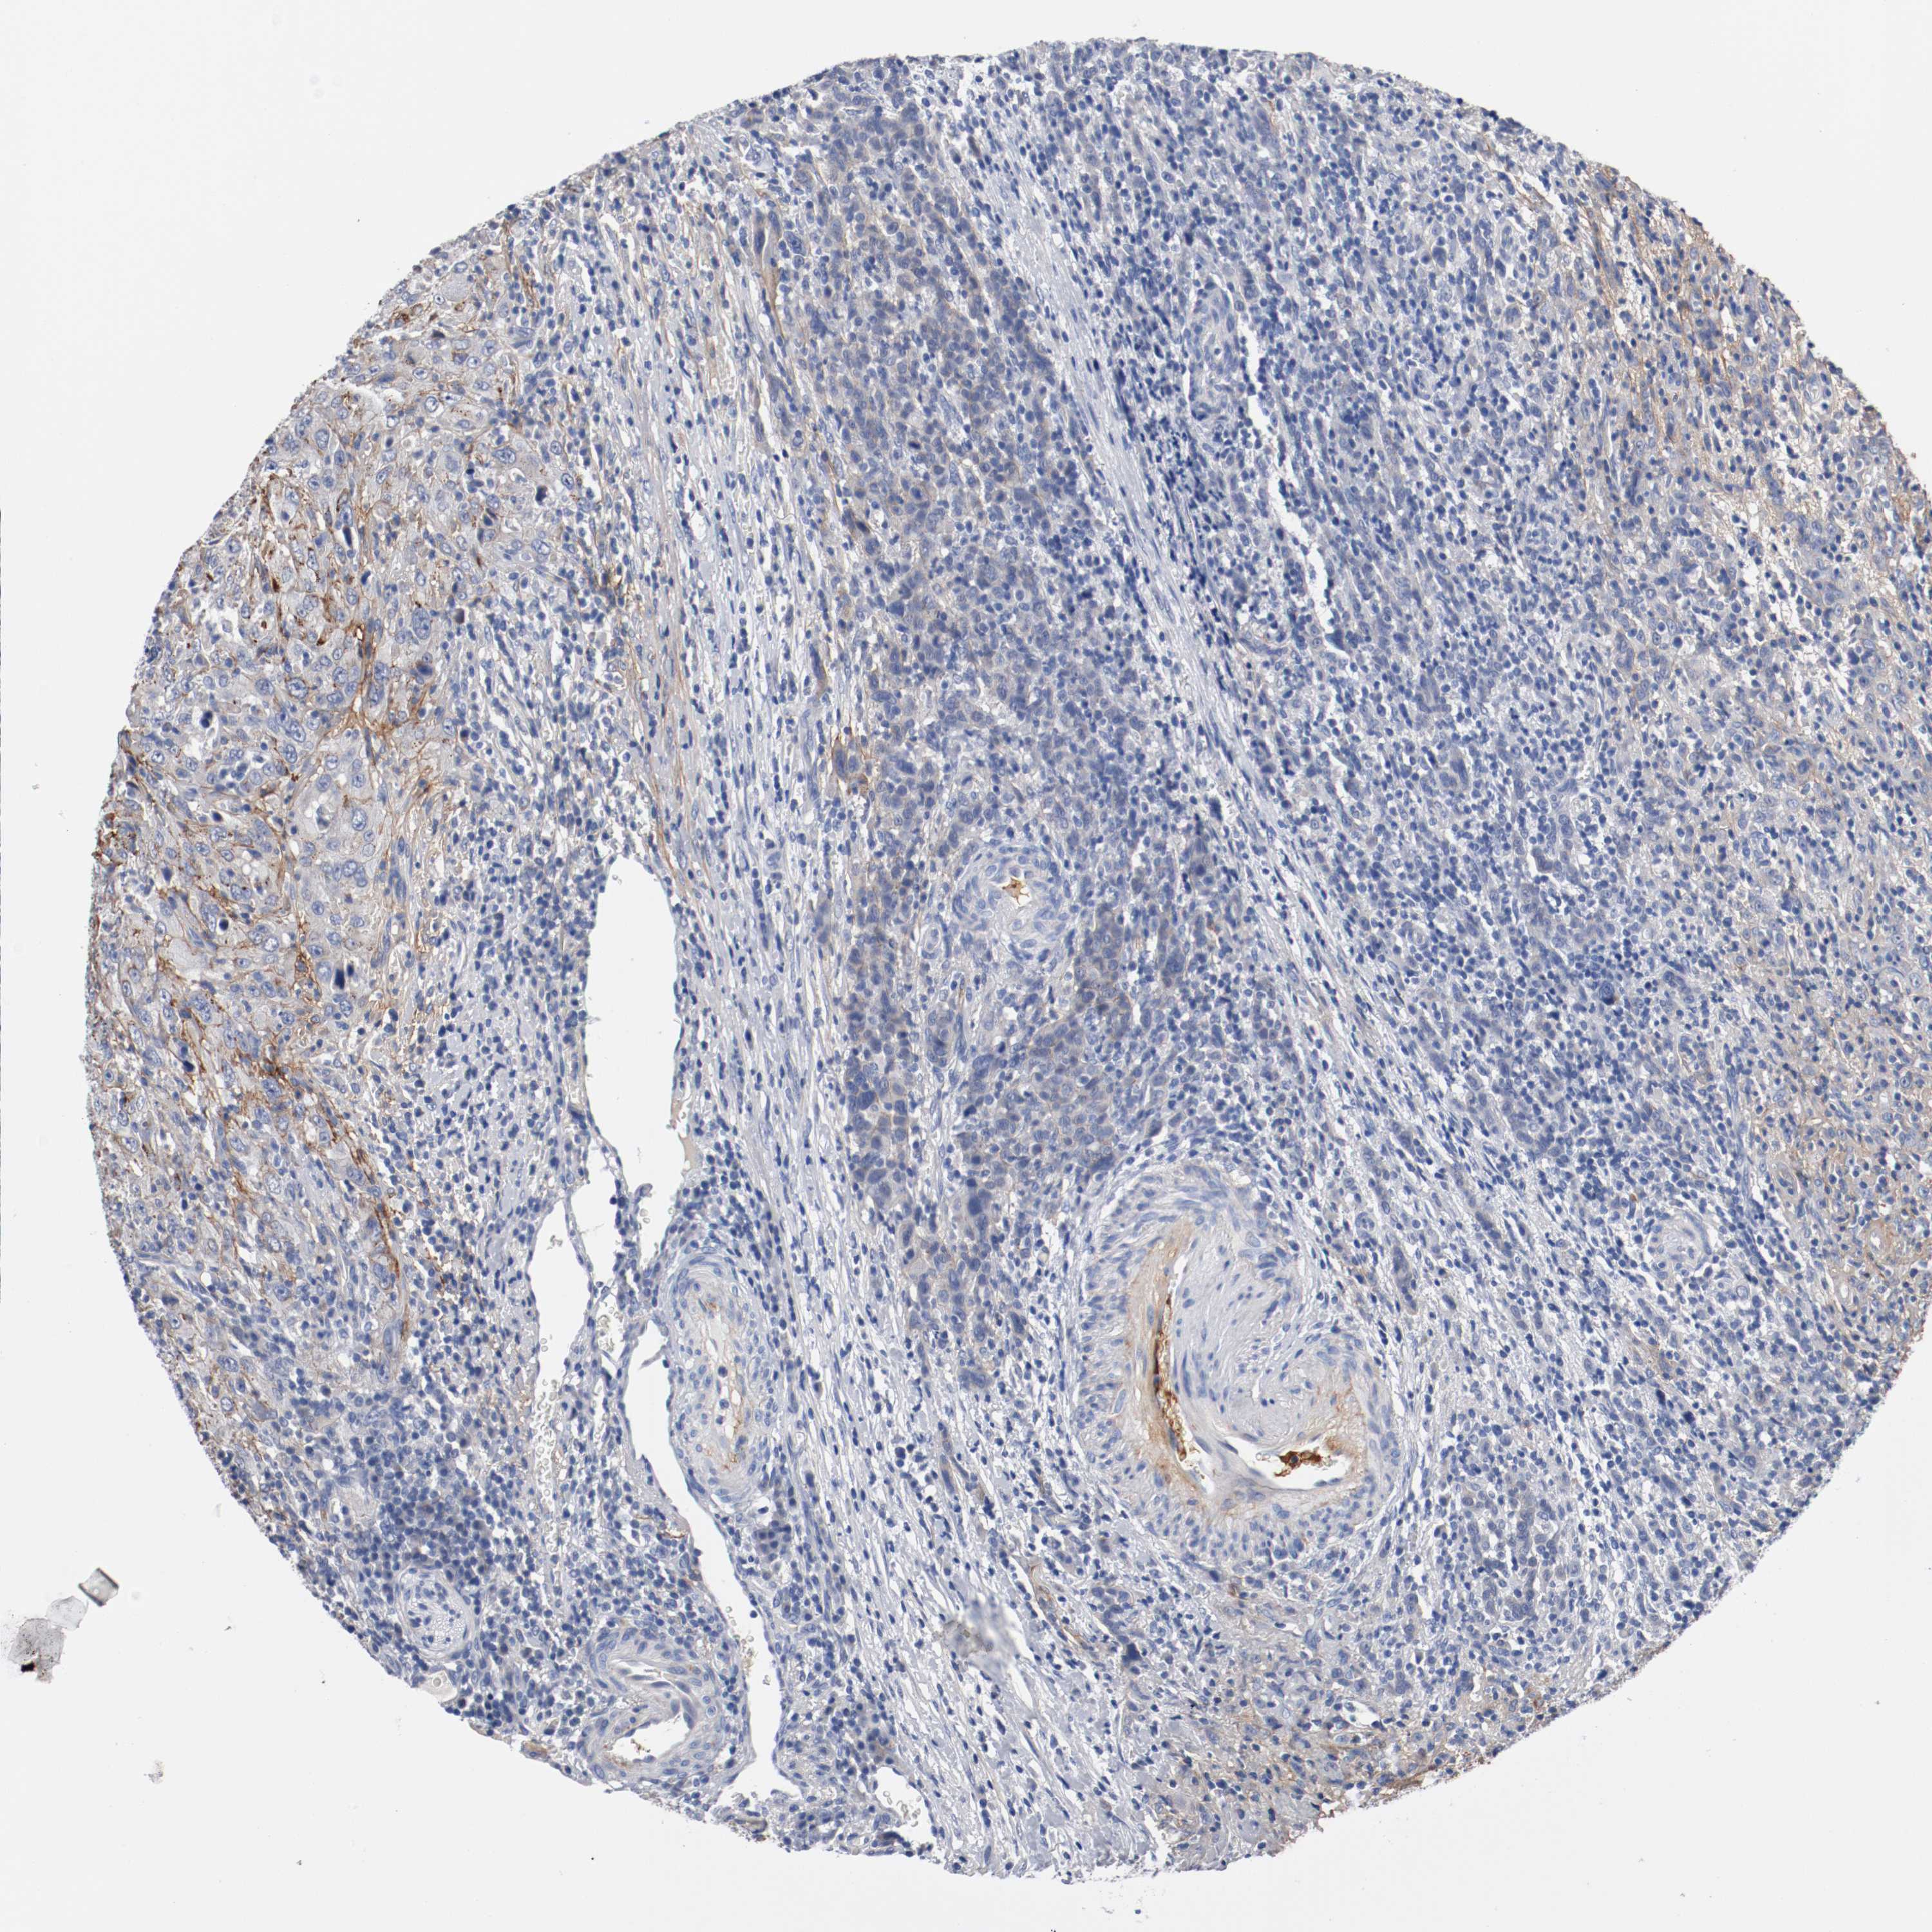

UROTHELIAL CANCER - Protein expressioni

A mouse-over function shows sample information and annotation data. Click on an image to view it in a full screen mode. Samples can be filtered based on level of antibody staining by selecting one or several of the following categories: high, medium, low and not detected. The assay and annotation is described here.

Antibody stainingi

Antibody staining in the annotated cell types in the current human tissue is reported as not detected, low, medium, or high, based on conventional immunohistochemistry profiling in selected tissues. This score is based on the combination of the staining intensity and fraction of stained cells.

Each image is clickable and will lead to virtual microscopy that enables deeper exploration of all samples and also displays staining intensity scores, fraction scores and subcellular localization as well as patient and tissue information for each sample.

Antibody HPA004823

Antibody CAB004592

Staining

High

Medium

Low

Not detected

Intensity

Strong

Moderate

Weak

Negative

Quantity

>75%

75%-25%

<25%

None

Location

Nuclear

Cytoplasmic/membranous

Cytoplasmic/membranous,nuclear

Urothelial carcinoma, High grade